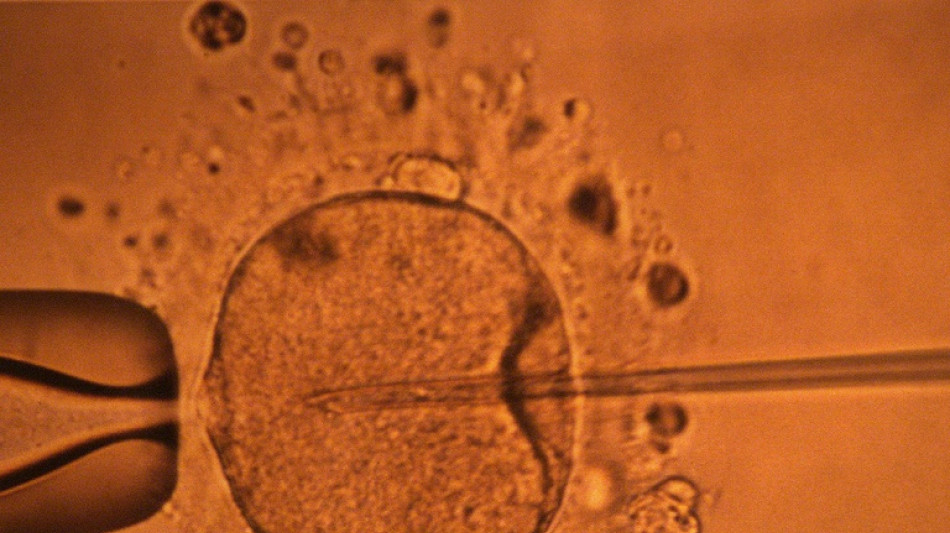

Une étude appuie l'hypothèse d'un déclin mondial de la concentration en spermatozoïdes / Photo: MARCEL MOCHET - AFP/Archives